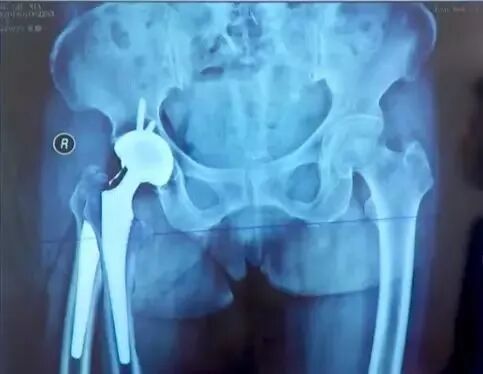

四、髋关节置换术后评估

术后评估内容:

①肢体长度:真实长度(髂前上棘到内踝长度);

②影像学长度(耻骨下沿连线通过双侧股骨同一高度)

③髋臼角度:外展角在35°-45°之间前倾角在15°-20°之间;

④髋臼位置:恰好贴近泪滴外绿的外侧,日杯缘应位于髋臼内外侧壁之间;

⑤假体触面:假体骨界面;假体骨水泥界面;骨水泥骨界面;

⑥股骨假体:颈干角、前倾角、柄-髓腔。

肢体长度:

真实长度(髂前上棘到内踝长度)测量即可;

影像学长度(耻骨下沿连线通过双侧股骨同一高度),有些患者可能影像学上看着不等长,这时候考虑是处于外旋位,摆到正常内旋位即可准确判断是否等长。